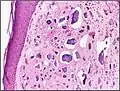

| Micrograph of calcinosis cutis. The calcification is purple (bottom of image). H&E stain. | |